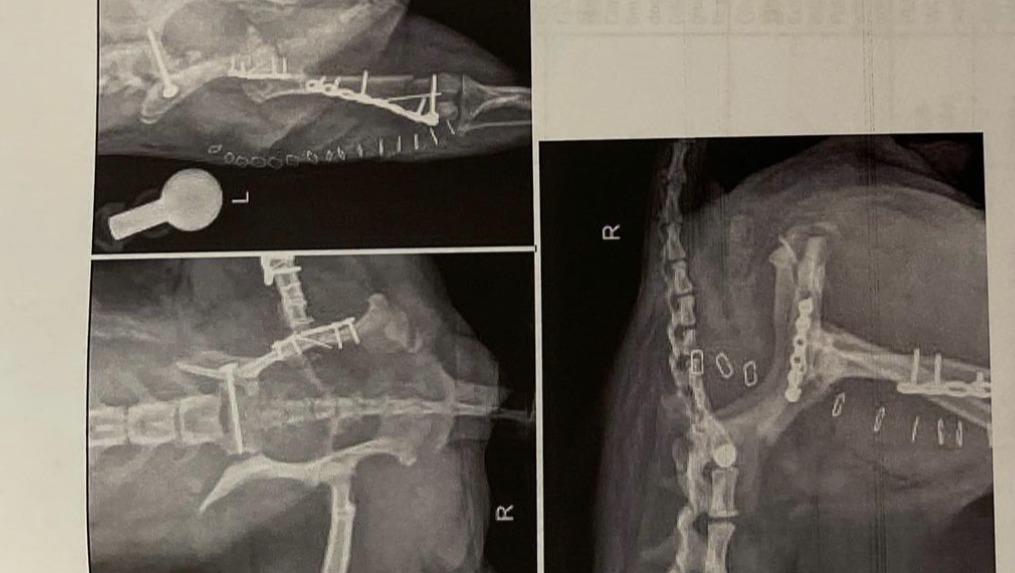

In April, I received a call that Aura had been lost. I left work and called every vet and animal hospital in the area until I found her. She had survived a traumatic injury. Aura had been run over by a car which left her with a broken left leg, shattered pelvis, and severe nerve damage in the right leg. She couldn’t walk and didn’t know if she would ever be able to.

Fast forward, Aura started to limp again severely over the past month. I took her to the vet, and she had to have another emergency surgery. Needless to say, this is all sooooo so expensive... It's been quite the year, but we're trying to stay optimistic! By donating - you'll be helping her SO MUCH with surgery costs, rehab, and the proper medication she needs to get better. She also will be sending e-licks/kisses to all of you :)